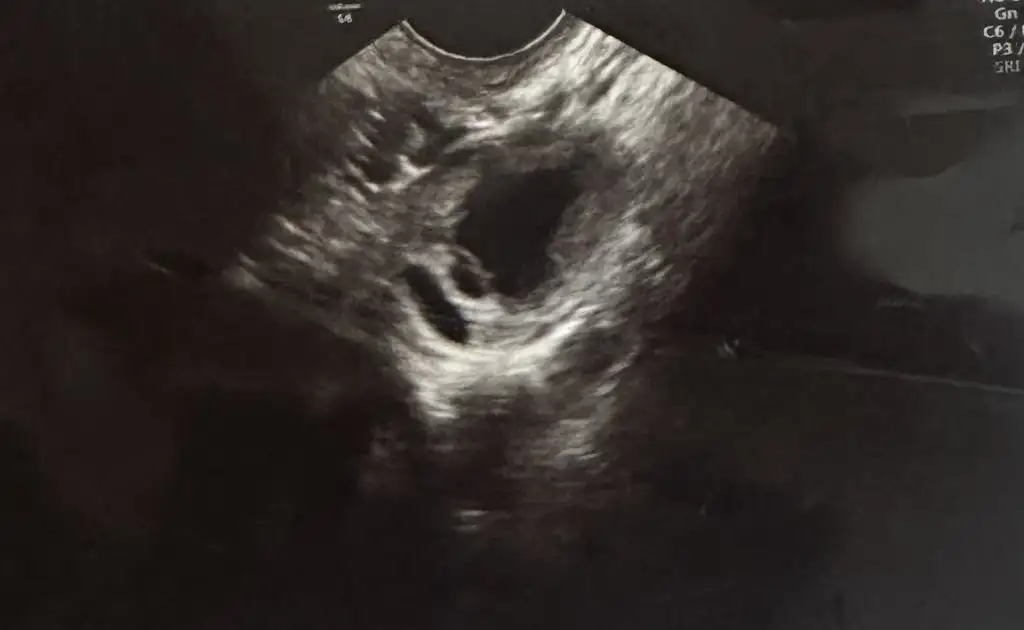

Sanki silik canım kaç gün var bat aKizlar bisey gorebilen var mi? Cok silik gördüm gibi ama?

5 gun var pazar bat gunuSanki silik canım kaç gün var bat a

Canım bende silik cizgi görüyorum, inşallah bebişin seninledirKizlar bisey gorebilen var mi? Cok silik gördüm gibi ama?

Net görünüyor benceArkadaşlar sabah yaptim